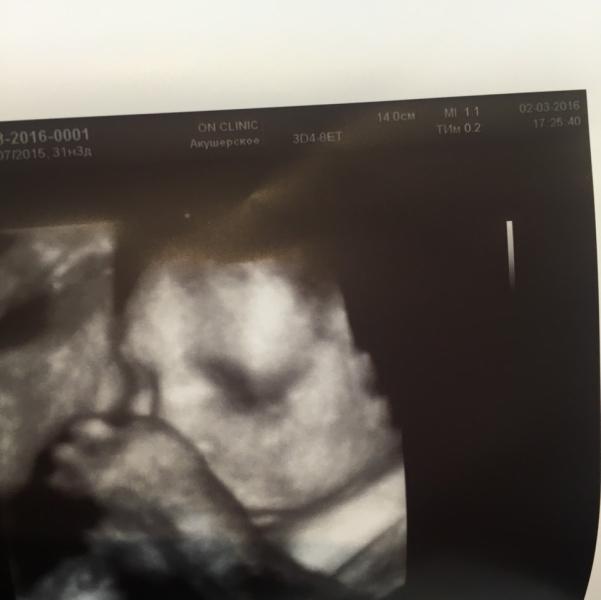

Сходила на узи Кемельбековой действительна 👍👍👍 все показала не куда не торопилась)) на втором скрининги был расширен кишечник и гэф, ттт сейчас все их нет)))

Вообще 31 неделя по узи соответствует 33 неделям, пол мне ещё на 12 недели говорили))) узи скрининг стоит 5600) отдельно и мошонку сфотографировали)))